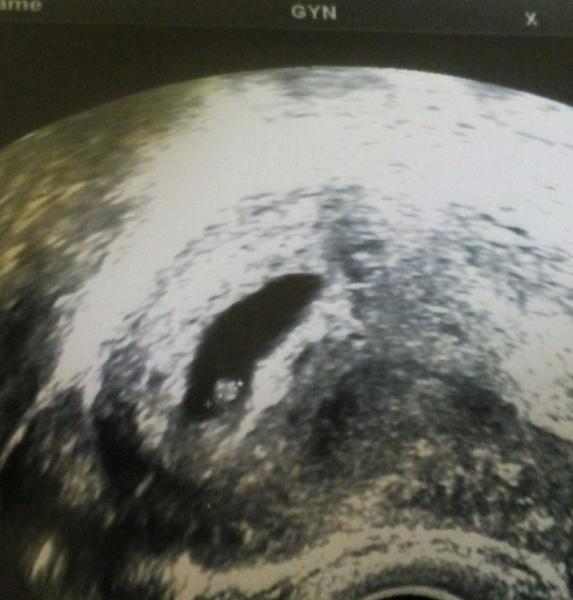

Ahoj holky,pridavam fotecku naseho malinkyho broucka.👶💕 jsme 6+2 a krasne nam bije srdicko😍 foto jsem dostala,protoze jsem byla ted na pohotovosti s tim,ze me boli v krku,nemohu polykat,mam rymu a mota se mi hlava... Tak me zkoukla celou... Nastesti to na antibiotika neni 😇 tak musime odpocivat a cucat pastilky 😊

Jinak fotečka krásná 😉